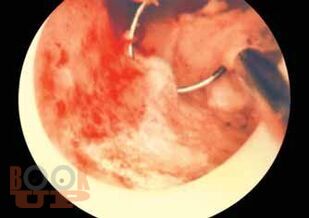

Presentation is simple, lucid and concise. Core knowledge (must-know areas) has been highlighted. Enriched with numerous flowcharts, tables, boxes, sketches and drawings. Consistent and uniform standard of information in all the chapters. Information is up-to-date and evidence-based. Key points at the end of each chapter and algorithms for easy and quick revision. Practical gynecology (chapter 38) with high quality colored illustrations and self-assessment questionnaire for the development of clinical and practical competence. Different color codes for the readers convenience quick reference. An illustrated atlas in gynecology, enriched with good-quality colored diagrams and photographs for ease of understanding and reproduction. Revised thoroughly with incorporation of new and updated content on the latest topics, including Minimally Invasive Surgery, General Gynecology, Reproductive Endocrinology, Urogynecology and Gynecologic Oncology. Orientation of surgical operations is reflected with profuse number of colored photographs, sketches, instruments and line drawings. Online access through www.dcdutta.com/www.hiralalkonar.com is available for viewing video clips of common gynecological operations and email access: h.kondr@gmail.com for questions, answers and discussions. Indispensable for medical students, trainee doctors and different postgraduate entrance examinations in India and abroad. Equally informative to nursing students, homeopathy and ayurvedic students as well as for general practitioners and practicing gynecologists. An authoritative and comprehensive textbook with guidelines and recommendations of professional and academic organizations.